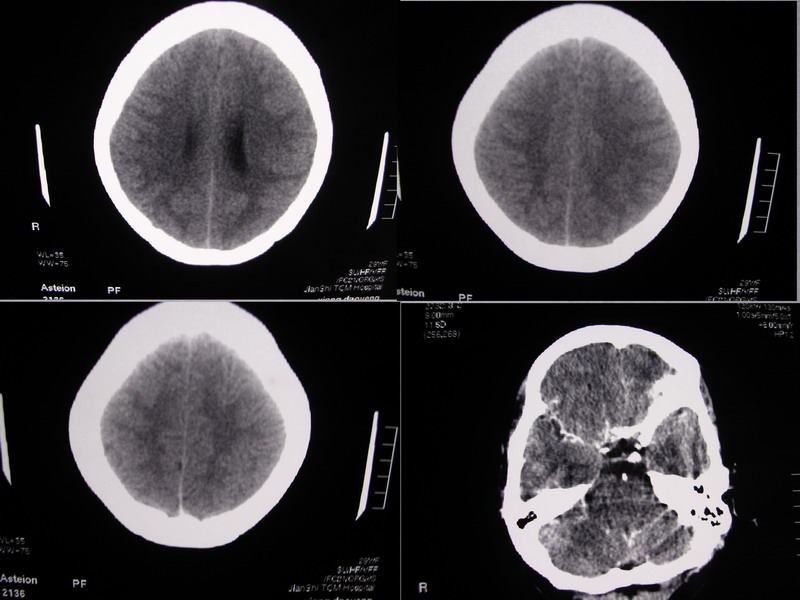

向××,女,29岁,二十天前高热,抗炎治疗后双眼斜视,肌无力,双下肢张力ii级。

可能是因为图片太小了,总感觉左侧颞叶和右侧额叶前部看的不是很舒服。

应该建议患者再做mri检查

双侧脑室有轻度扩大,增强看脑沟裂显示还是模糊的.时间较长应该考虑脑膜炎.

看不出有什么异常,建议行mri检查.